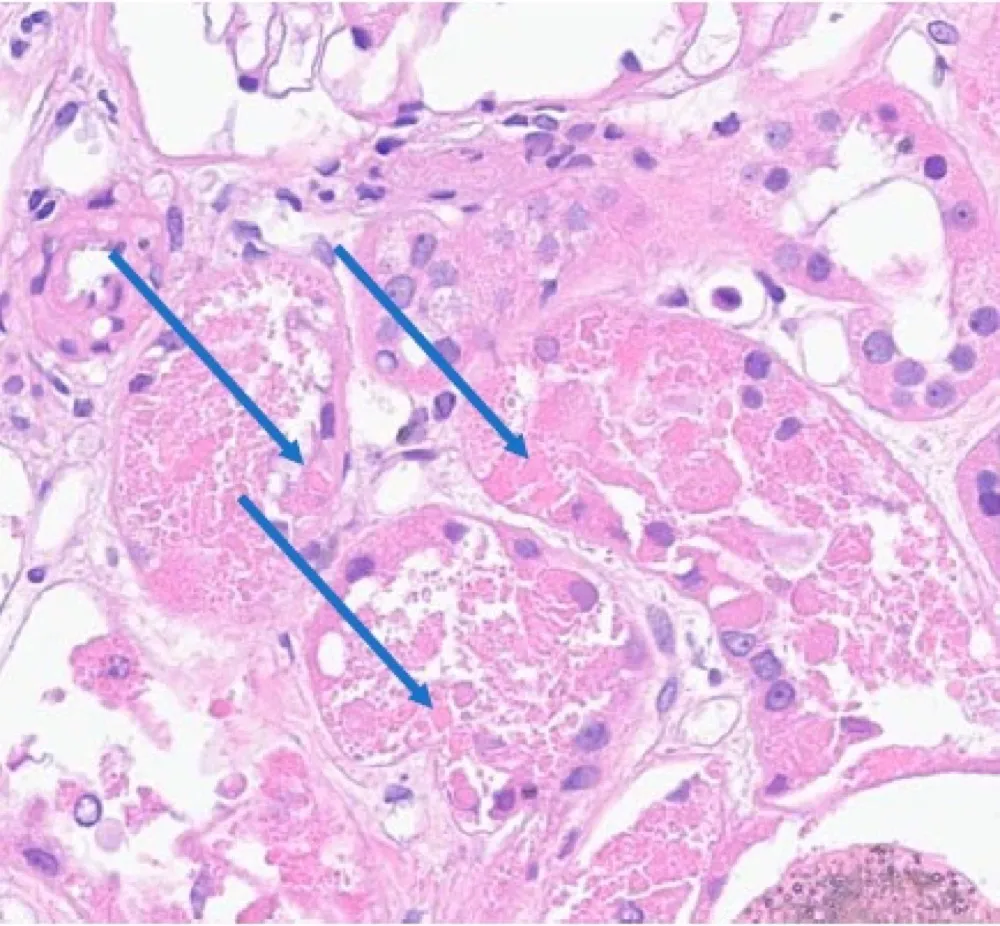

IRA + Icterícia: Um Caso que Exige Investigação Detalhada

IRA + Icterícia: Um Caso que Exige Investigação Detalhada